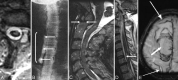

Despite extensive imaging, a source of bleeding is often not evident during the evaluation of patients with superficial siderosis (SS) of the central nervous system. An intraspinal fluid-filled collection of variable dimensions is frequently seen on spine MR imaging in patients with idiopathic SS. A similar finding has also been reported in patients with craniospinal hypotension. This review discusses the role of multitechnique imaging in the work-up of patients with SS and focuses on recent developments.